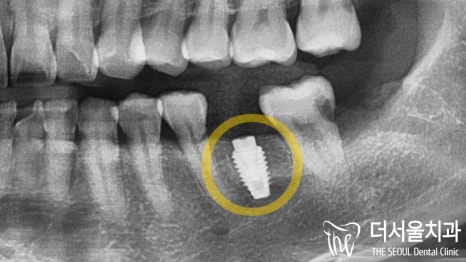

이후 컴퓨터 분석을 통해

30대 임플란트 수술의 세부적인 계획을 세웠습니다.

제작된 가이드를 사용하여

정해진 위치에 식립을 마무리했습니다.

젊은 연령대라 앞서 말씀드렸던 것처럼

골융합도 문제없이 잘 일어났습니다.